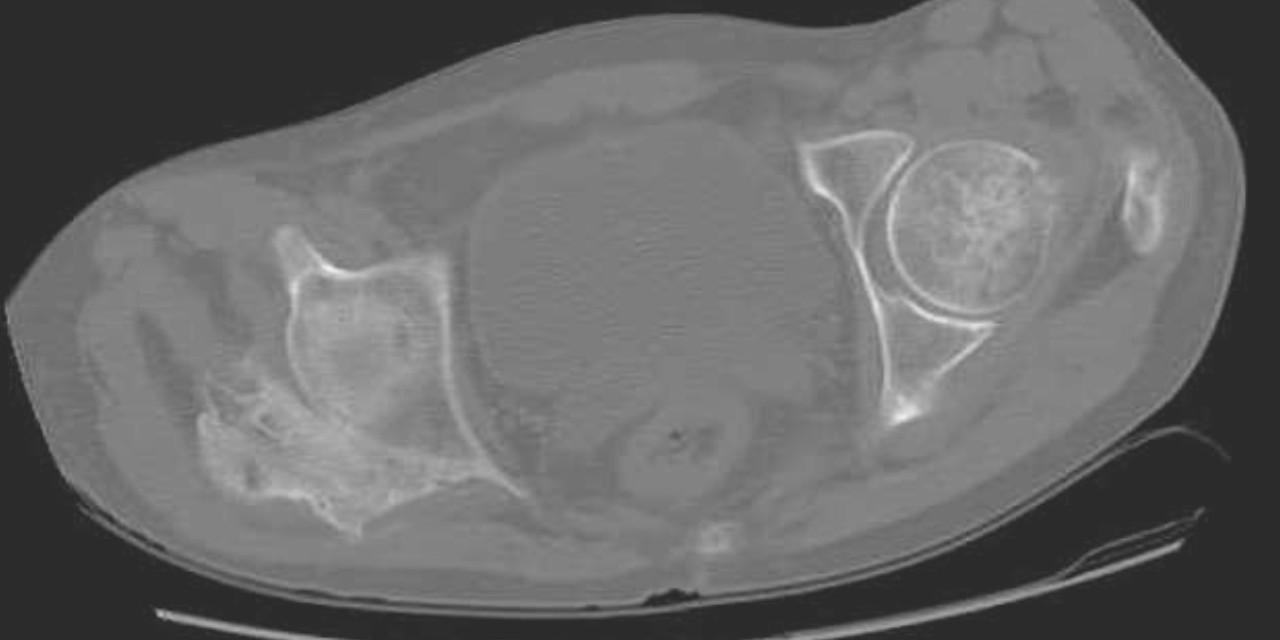

Figure 1 demonstrates early calcification of a myositis ossificans lesion in the left triceps muscle. As is characteristic, there is an outer shell of bone with a lucent central region. Figure 2 is a more mature, well-defined lesion with a dense periphery at the medial aspect adjacent to the femur.